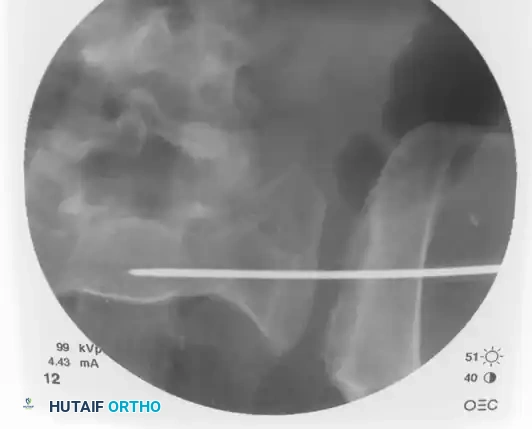

Once the trajectory is perfected, advance the guidewire under power across the sacroiliac joint and into the sacral ala.

Stop advancing just before the midline. Confirm safe passage on both the inlet and outlet views.

Finally, check the lateral sacral view to ensure that the guidewire is entirely contained within the osseous boundaries of the sacral body and has not breached the anterior alar slope.